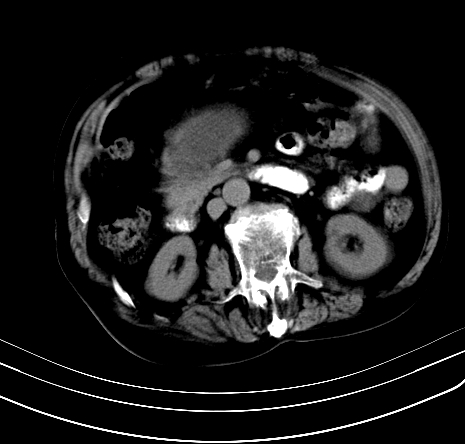

上腹部疼痛不适,行ct检查

胰腺明显肿大,密度减低,考虑慢性胰腺炎,假性囊肿形成不除外。

胰腺明显肿大,考虑慢性胰腺炎假性囊肿形成,不除外胰腺癌可能。

胰腺较明显扩大,胰周有渗出;肾周筋膜有增厚渗出,以左肾为著。应考虑急性胰腺炎。

慢性胰腺炎,假囊肿形成,脂肪肝。